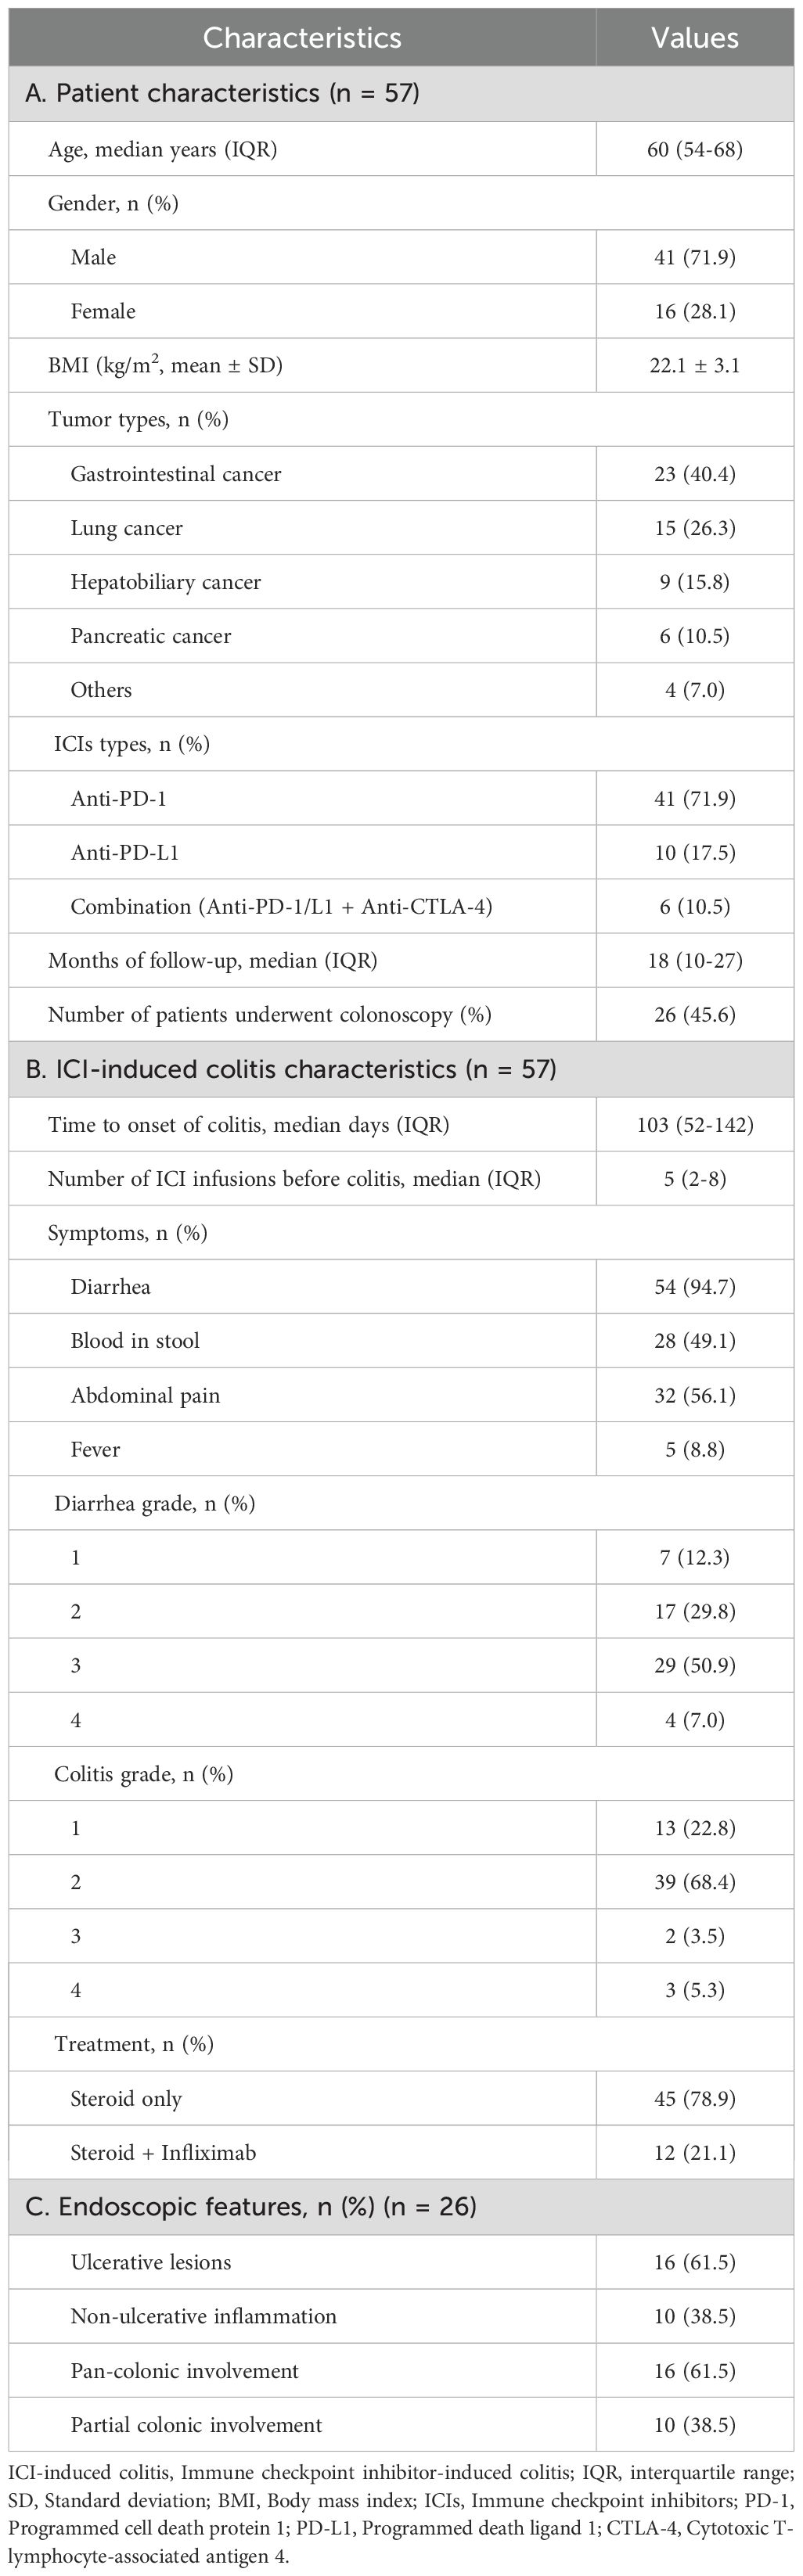

A total of 57 patients with ICI-induced colitis were included in this study (Figure 1). The patient’s characteristics are presented in Table 1A. The cohort comprised 41 males (71.9%) and 16 females (28.1%), with a median age of 60 years (interquartile range [IQR], 54-68). Gastrointestinal cancer represented the most common tumor type (40.4%), followed by lung cancer (26.3%), hepatobiliary cancer (15.8%), and pancreatic cancer (10.5%). Regarding the type of ICI treatment, 41 patients (71.9%) received anti-PD-1 monotherapy, 10 (17.5%) received anti-PD-L1 monotherapy, and 6 (10.5%) received combination therapy with anti-PD-1/PD-L1 and anti-CTLA-4 therapy. Colonoscopy was performed in 26 patients (45.6%). The median follow-up duration was 18 months (range, 2-79).

Figure 1. Flow diagram of the study design. A total of 734 patients were screened, of whom 57 patients met the eligibility criteria and were included in the final analysis. ICIs, Immune checkpoint inhibitors; IBD, Inflammatory bowel disease.